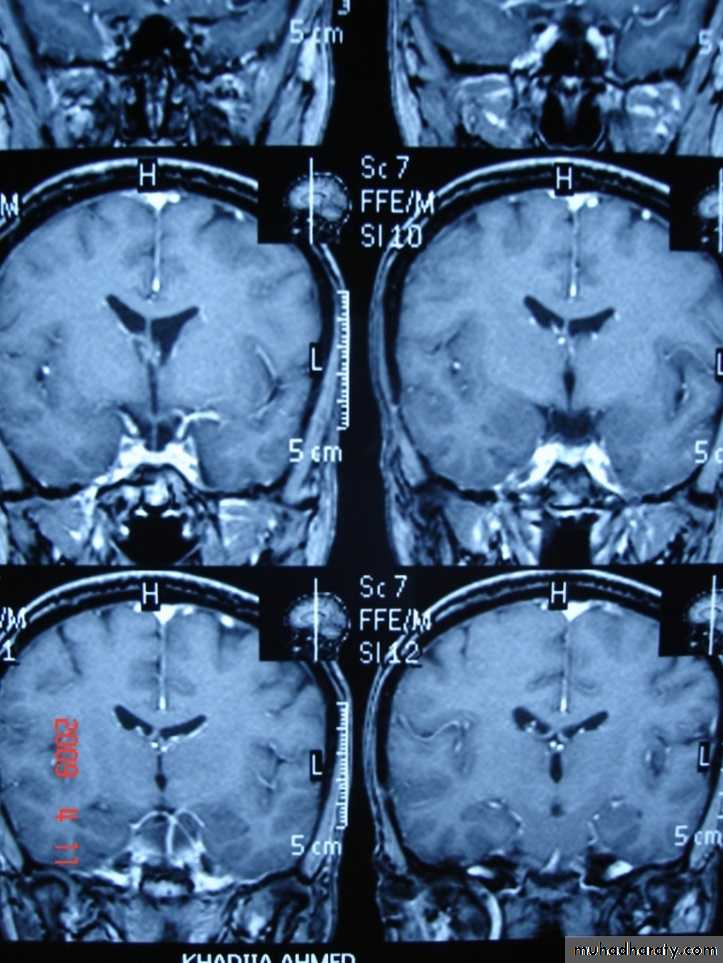

CORONAL SECTION OF BRAIN ( T1w post contrast injection)

Coronal T1-weighted MRI image through a brain lesion showing homogeneity of the lesion, lack of a perceptible wall, lack of internal complexity, and CSF signal intensity. There is associated remodeling of the adjacent calvarium and brain displacement. These imaging features are typical of an arachnoid cyst.